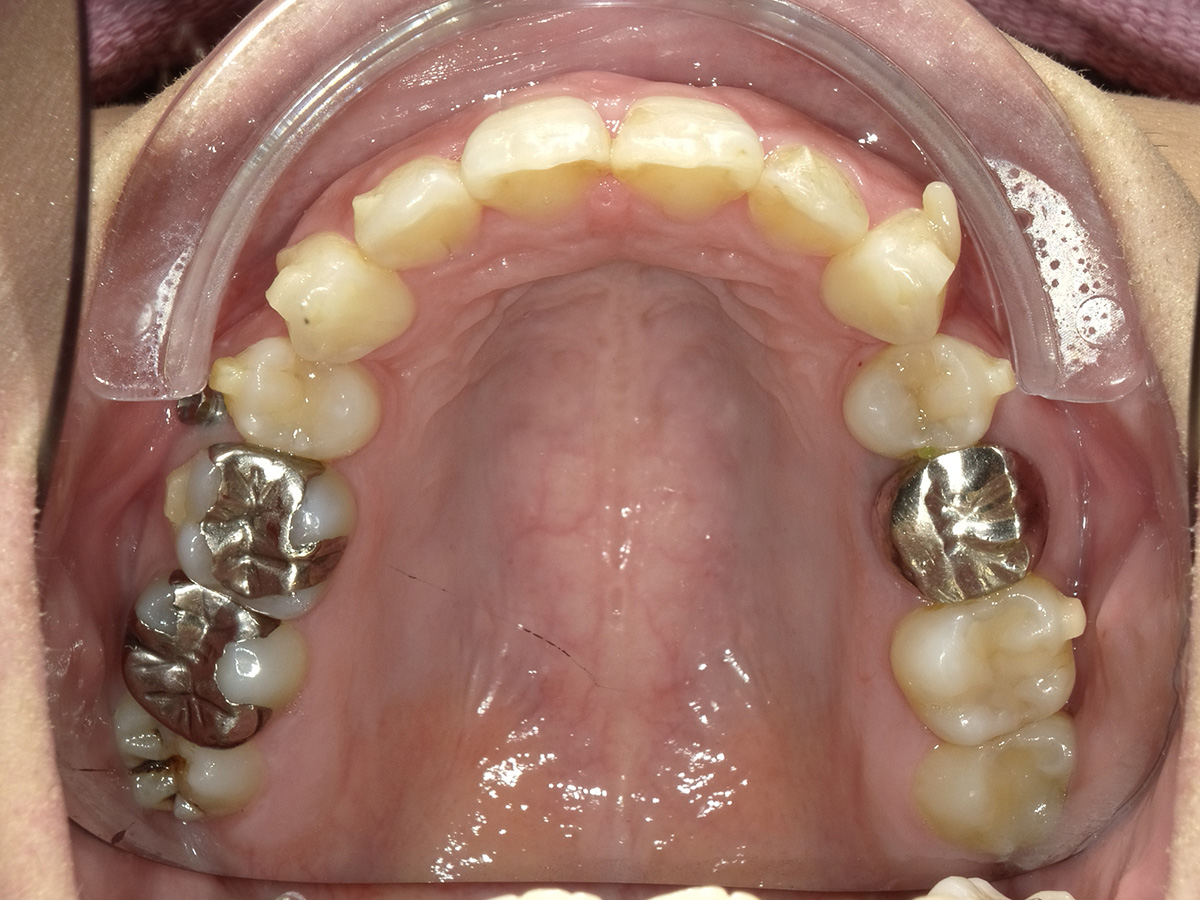

Before After

上顎前突(口ゴボ)

症例概要 / Case details

- 治療名: インビザライン(抜歯矯正)

- 主訴: 出っ歯を治したい

- 期間・回数: 7ヶ月 / 来院3回

- 費用の目安(自費・税込換算の目安): 770,000円(税込)

- リスクについて:使用時間に応じて歯の移動の結果が変わる場合があります。

治療内容の要点

口元を下げるために、前から4番目の歯(第一小臼歯)を抜歯し、そのスペースを利用して前歯を後ろに下げました。

歯は骨に埋まっているため、CT撮影をすることで骨の厚みを把握し、その中で歯が安全に収まるように治療計画を組みながら確実に移動させていきました。

無事前歯が後方に移動し、Eラインが綺麗に整っています。